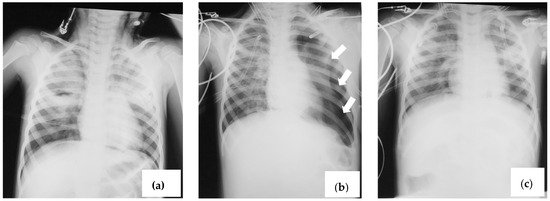

2.2. Case 2